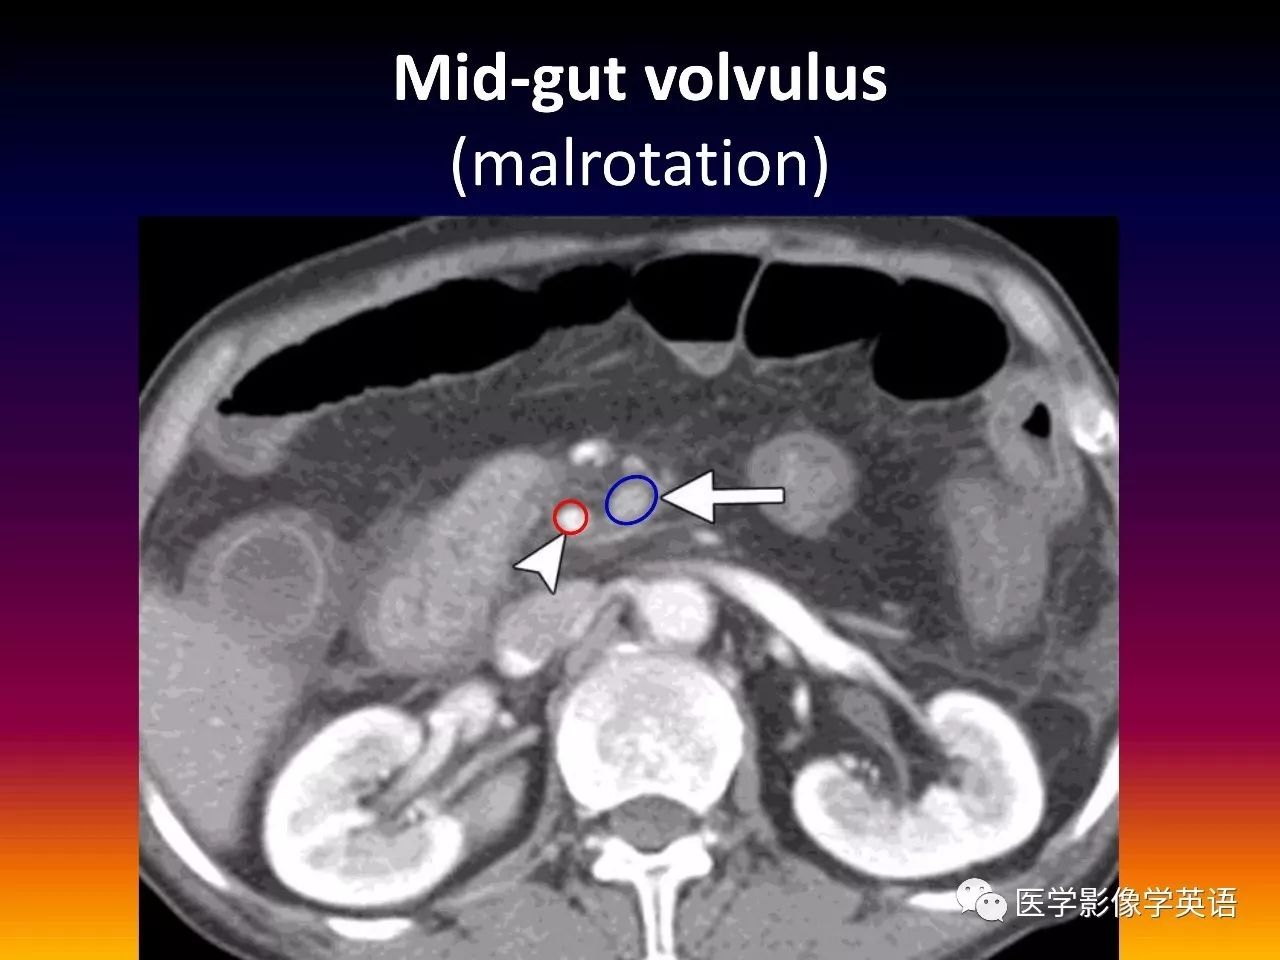

82. Mid-gut volvulus (malrotation)

83. Mid-gut volvulus (malrotation)

45. Volvulus Gastric volvulus Organo-axial Greater curvature above lesser curvature Mesentero-axial Gastric antrum above gastric fundus Midgut volvulus Malrotation (SMV to the left of SMA) Whirl sign Colonic volvulus Sigmoid Whirl sign Cecal Whirl sign